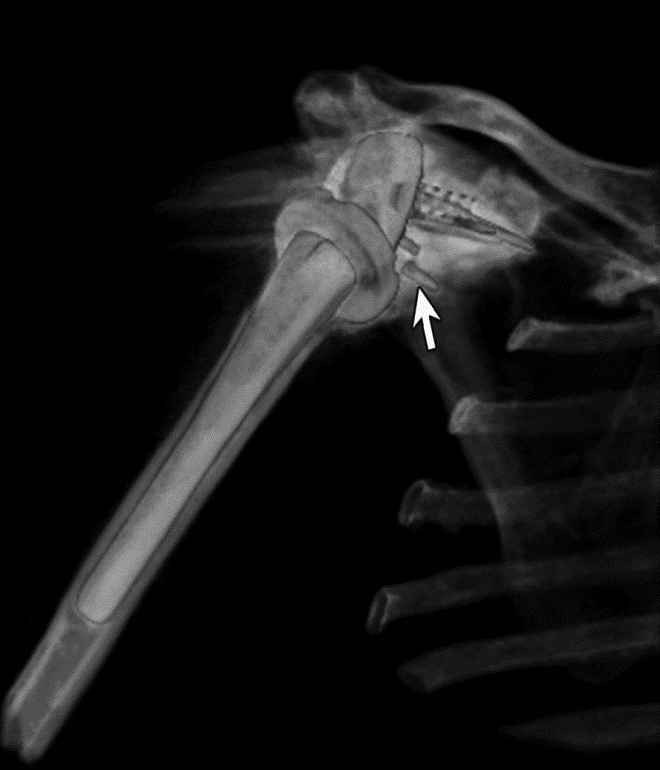

Variable Hardware Attenuation. (A) CT scout image demonstrates heterogeneous density of glenoid components of reverse total shoulder arthroplasty. (B) Axial CT image shows metallic glenosphere (curved arrow) positioned appropriately on less dense metaglene (straight arrow)

Periprosthetic 3D Reconstruction. (A) 3D reconstruction of osseous anatomy surrounding right total shoulder arthroplasty without dual-energy technique demonstrates significant artifact limiting evaluation of hardware and glenohumeral joint. (B) Dual-energy CT 3D reconstruction focused on metallic hardware demonstrates excellent visualization of hardware with metaglene screw fracture (arrow). Dual Energy CT. (A) Axial CT image acquired with dual energy technique demonstrates minimal artifact secondary to sacroiliac joint screws. (B) Coronal multi-planar reformation demonstrates excellent visualization of the osseous anatomy and hardware with further minimization of artifact.